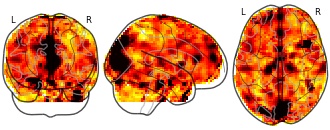

"description": "Multi-modal analysis in BPD. Brain regions exhibiting smaller gray matter and enhanced activation during emotion processing in BPD compared to healthy controls. Note: Results were thresholded at p<.0025. Note2: Results were updated (see Erratum for this publication).",